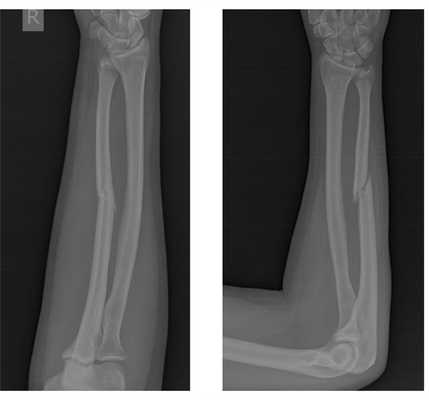

До операции:

После операции:

После операции